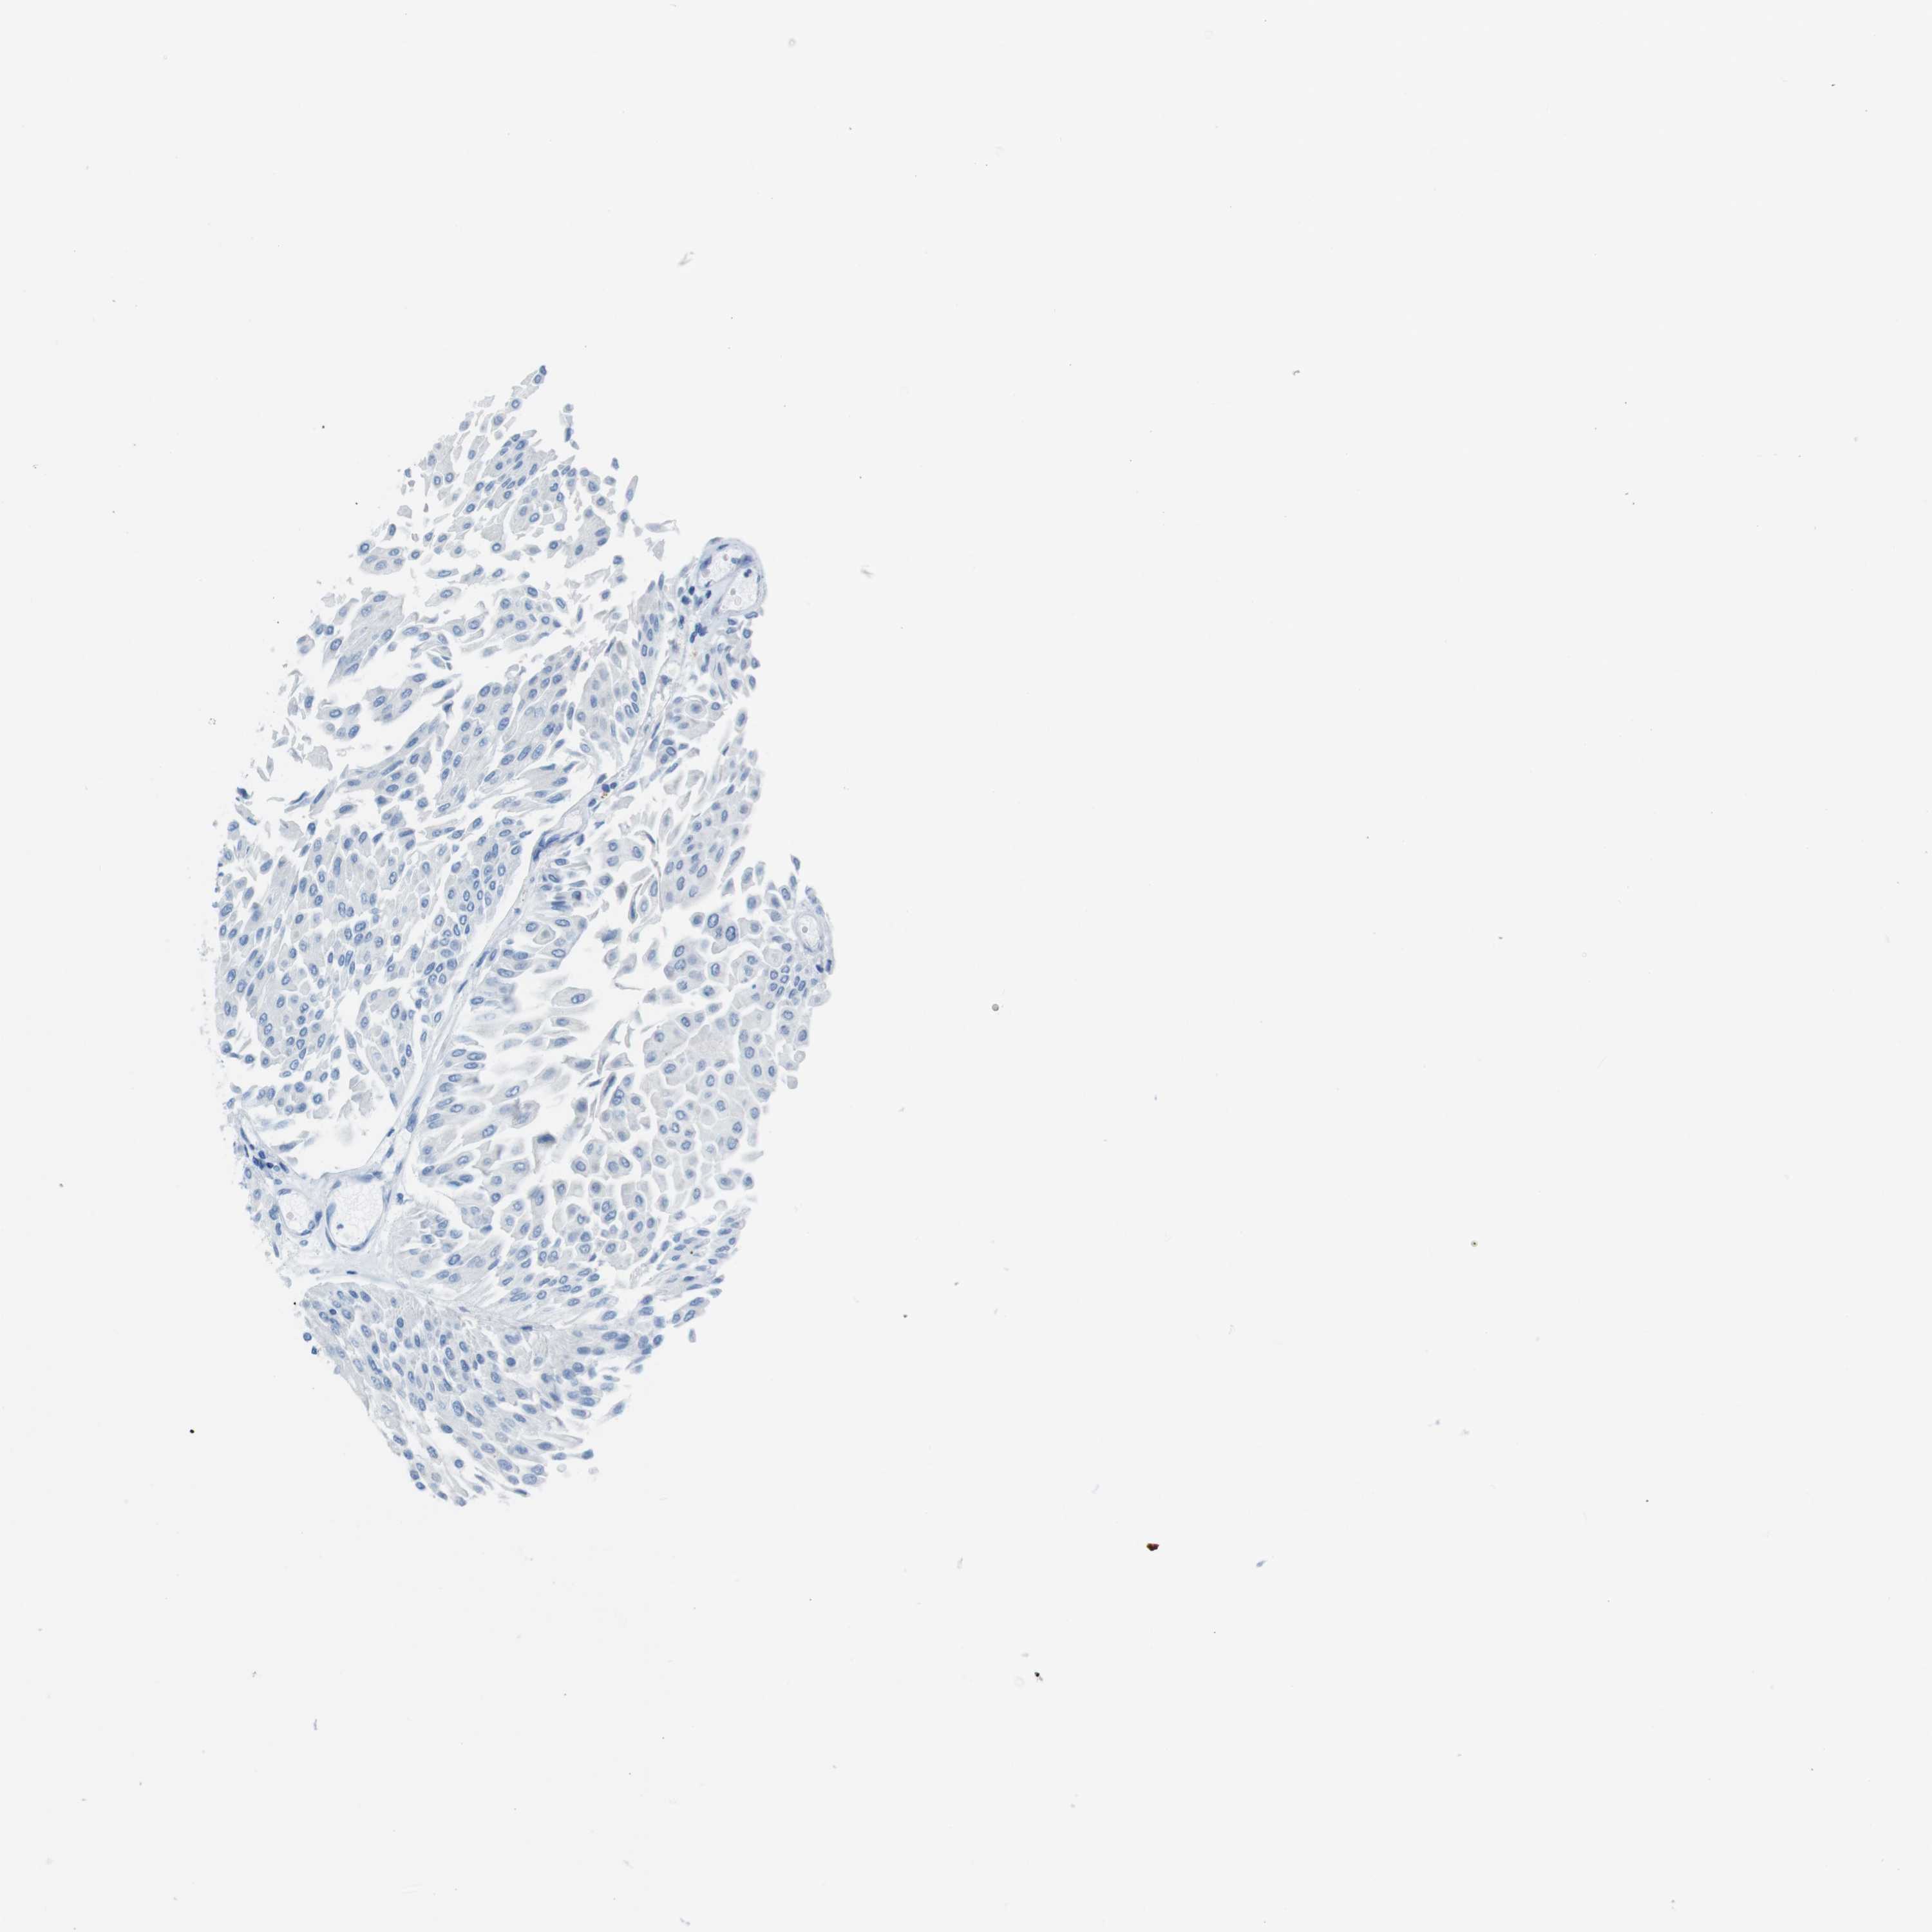

UROTHELIAL CANCER - Protein expressioni

A mouse-over function shows sample information and annotation data. Click on an image to view it in a full screen mode. Samples can be filtered based on level of antibody staining by selecting one or several of the following categories: high, medium, low and not detected. The assay and annotation is described here.

Antibody stainingi

Antibody staining in the annotated cell types in the current human tissue is reported as not detected, low, medium, or high, based on conventional immunohistochemistry profiling in selected tissues. This score is based on the combination of the staining intensity and fraction of stained cells.

Each image is clickable and will lead to virtual microscopy that enables deeper exploration of all samples and also displays staining intensity scores, fraction scores and subcellular localization as well as patient and tissue information for each sample.

Antibody HPA013392

Antibody HPA015600

Antibody CAB004417

Staining

High

Medium

Low

Not detected

Intensity

Strong

Moderate

Weak

Negative

Quantity

>75%

75%-25%

<25%

None

Location

Nuclear

Cytoplasmic/membranous

Cytoplasmic/membranous,nuclear

Urothelial carcinoma, Low grade

Urothelial carcinoma, High grade